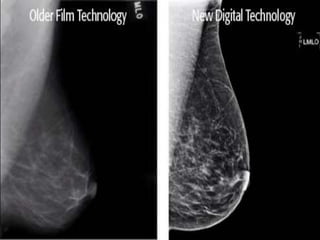

ADVANTAGES OF DIGITAL

MAMMOGRAPHY

1. Acquired in less than a minute as compared to

conventional mammography .

2. Spot view digital systems are available to help

guide breast biopsy .

3. Superior contrast resolution especially in dense

breast tissues

4. Offers the possibility of three dimensional breast

tomography using relatively low doses .

DRAWBACKS

 Until ways are found to increase the spatial

resolution of digital mammography, conventional

film mammography will remain better able to detect

subtle tissue changes such as microcalcifications.

 In dense breast tissues even digital mammography

may overlook some lesions that are masked by

overlying structures